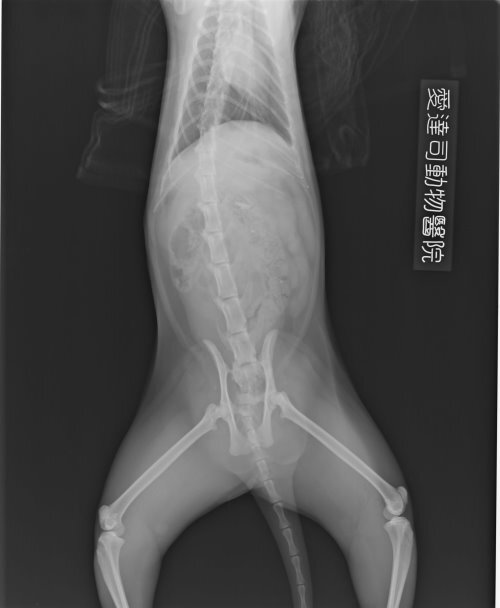

- 編號: 2005

主題: 車禍急傷 申請者姓名: 林素蘭 花色: 申請日期: 2013-06-03 23:43:51 申請者部落格: 申請者臉書網址: 所在縣市/合作醫院: 新北市/愛達司動物醫院 治療費用: 16867元 需求人數: 35人 已結案 (2013-06-27 14:20:08) 報名人員: philip x4(已付款)、Linda Wang(已付款)、Weili Chang x4(已付款)、吳毓軒 x2(已付款)、Emily Chou x10(已付款)、treaci(已付款)、賴霂菈(已付款)、黃亞凡(已付款)、戀糖bear x2(已付款)、你這樣(已付款)、Monica Wang(已付款)、點心(已付款)、小飛仔(已付款)、Kate(已付款)、miraai x2(已付款)、Bubu Wang x2(已付款)、 候補人員: sara1204、Suegie、 動物病情說明: 開車行經新店目睹貓咪被車子撞上,貓拖著雙腿在地上爬行,車來車往場面驚心,顧不得車上無任何工具,拿了厚塑膠袋衝到馬路上,試圖要抓牠,深怕這一錯過,貓就不見,或者一不小心又會被其他車輛撞到,一碰觸到貓,他立刻驚恐的想要掙脫,一回身拼命的咬,顧不得滿手鮮血,裝到袋子裡緊緊抱在懷裡,衝回去車上,打電話跟協會求助,送到協會配合的醫院,貓咪因為撞擊骨盆腔骨折,屁股附近的皮膚擦傷脫落,加上貓咪非常緊張,疼痛不願意進食,打了十幾天點滴,每天清創都唉唉叫,經過四十幾天的治療,屁股的傷口復原良好,因為骨盆尚未進行手術,怕癒後會有骨盆狹窄的問題,出院後先安置於家中照顧追蹤,大部分與到需要幫助的貓咪都會自己負擔醫療費用,但這隻貓咪傷勢嚴重,近期遇到的傷病需要醫療的貓咪很多,實在無力再負擔,自付三分之一的醫療費用八千多元,其餘還請各為幫幫忙。謝謝!